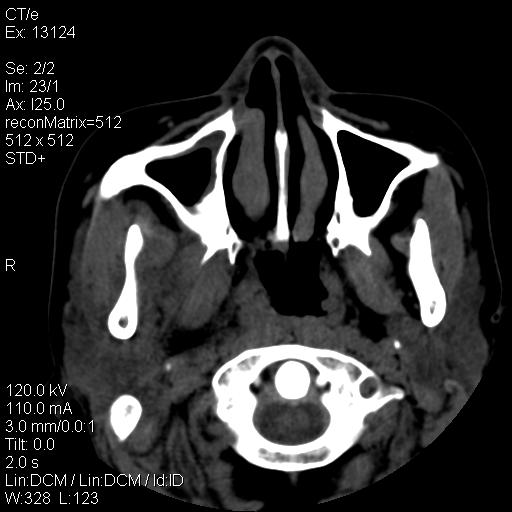

标题: CT18257:女,29岁,右下磨牙痛 [打印本页]

标题: CT18257:女,29岁,右下磨牙痛

女,29岁,右下磨牙痛,因产后2月,故未治疗。现右颌肿痛伴张口困难。请大家看看右侧鼻咽部、口咽部是否

2.右侧上颌窦炎症、两侧下鼻甲肿大

1)考虑右侧下颌区软组织脓肿(牙源性)。2)鼻咽部炎性改变;建议追踪复查。3)右侧上颌窦炎。4)双侧下鼻甲黏膜肥厚。

1)考虑右侧下颌区牙源性软组织脓肿。2)右侧上颌窦炎。3)双侧下鼻甲黏膜肥厚。4)鼻咽部炎性改变;建议追踪复查。